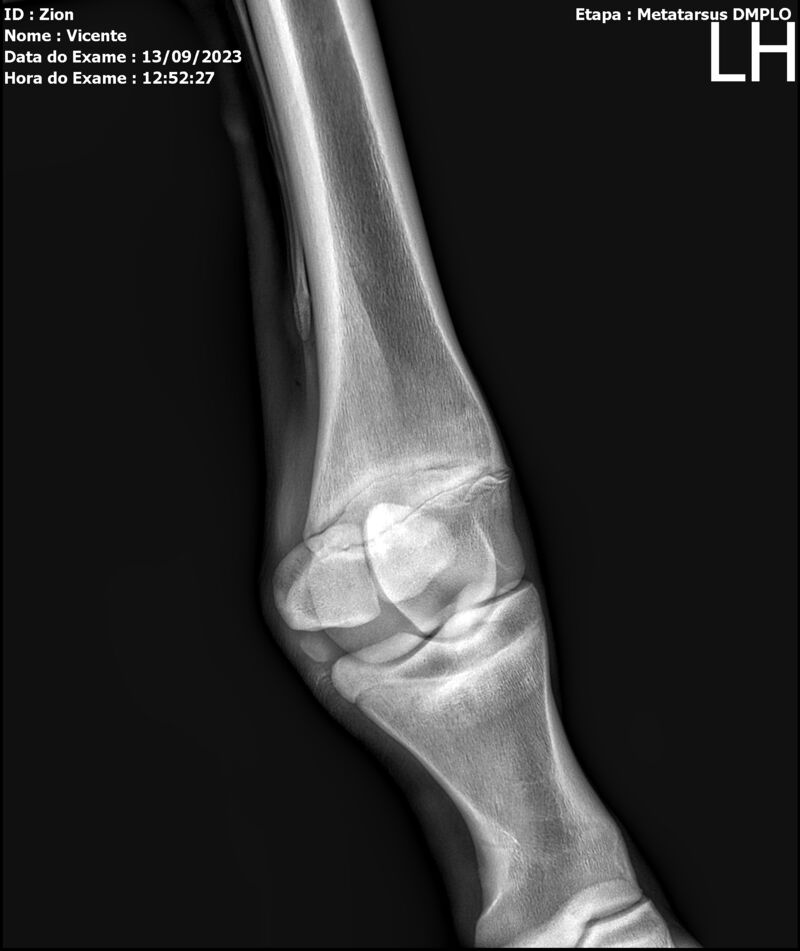

ZION ZC

Raça: BRASILEIRO DE HIPISMO

Sexo: MACHO - POTRO

Nascimento: 17/12/2022

Altura Aproximada: 1,51

Pel.: CASTANHO

Registro: EM AND

Vend.: VICENTE CONTE

Local : PORTO FELIZ/SP